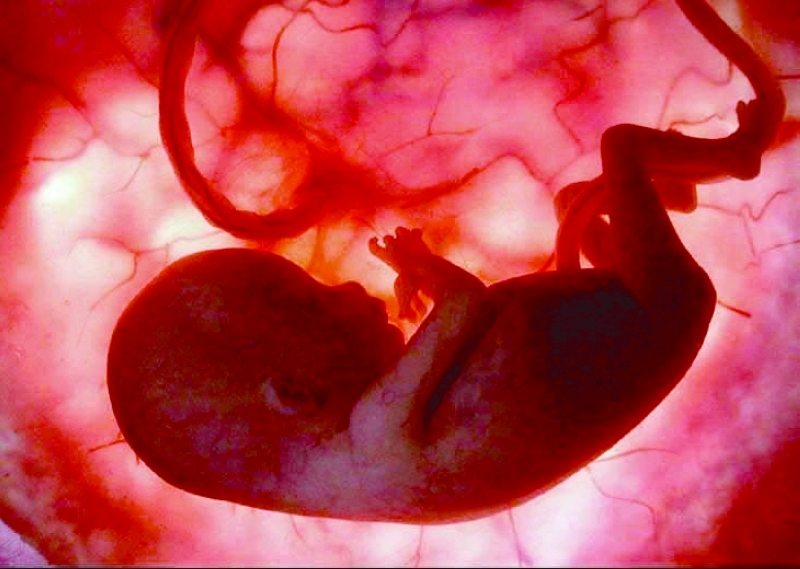

قالت الدكتورة منى خلفان رئيس قسم النساء والولادة بمستشفى القاسمي إن القسم يعاني من عدد المريضات المراجعات لعنبر الولادات دون مراجعات سابقة لعيادات المستشفى الأمر الذي يضع المريضة وجنينها تحت مخاطر اضافية، وذلك لعدم إحاطة الطبيب المستقبل للحالة بتفاصيل التاريخ المرضي للمريضة أو أي مضاعفات قد تكون حدثت خلال الحمل ولم يتم اكتشافها لعدم المراجعة الدورية للعيادات، لافتة الى أن بعض الأمهات يحضرن الى عنبر الولادة دون الحصول على تصوير دقيق للجنين أثناء الحمل الأمر الذي يؤدي الى عدم اكتشاف تشوهات الأجنة الا بعد الولادة وذلك لعدم التخطيط المسبق لاستقبال مثل تلك الحالات وكيفية التعامل معها.

ولفتت خلفان الى أن بعض حالات الولادة المبكرة لا يوجد سبب يمكن تفاديه فيها، وذلك نتيجة لعدم المراجعة الأولية، فتتطور الحالة الى تسمم حمل ما يشكل خطراً كبيراً على الأم وجنينها، كما أن بعضهن لا يشخص السكر لديهن باكراً في الأشهر الأولى من الحمل ما يزيد من فرصة ولادة طفل مشوه، وفي المراحل الأخيرة من الحمل يسب زيادة كبيرة في وزن الطفل ما يجعله اكثر عرضة للمضاعفات التي تحدث أثناء الولادة، مثل الشلل الاربي للذراع، منوهة الى ضرورة المراجعة خلال الأشهر الثلاثة الأولى، لأن التصوير خلالها يحدد وبدقة عمر الجنين، أما بعد الـ 3 أشهر الأولى فهناك فروقات فردية يتعذر معها تحديد عمر الجنين بدقة، كما أن أوزان الولادة الطبيعية بعد الولادة تتراوح ما بين 50،2 و4 كيلوغرامات، كما أن المراجعة المنتظمة تساعد الأم الى الوصول الى حمل آمن مع جنينها لأن خلالها يتم تشخيص أي حالات مرضية مصاحبة للحمل، فيتم التعامل معها في وقت مبكر ما يقلل من حدوث أي مضاعفات.